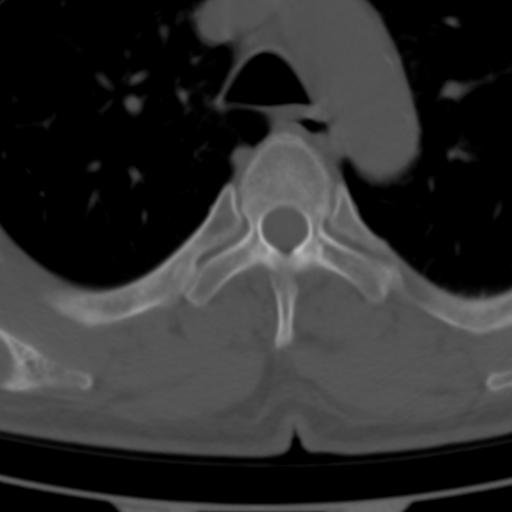

标题: CT25189:胸椎ct,请会诊!

既往食管癌,现行ct检查!

中上段食道癌,椎体轻度退变。

支持中上段食道癌,椎体轻度退变,必要时做ect。